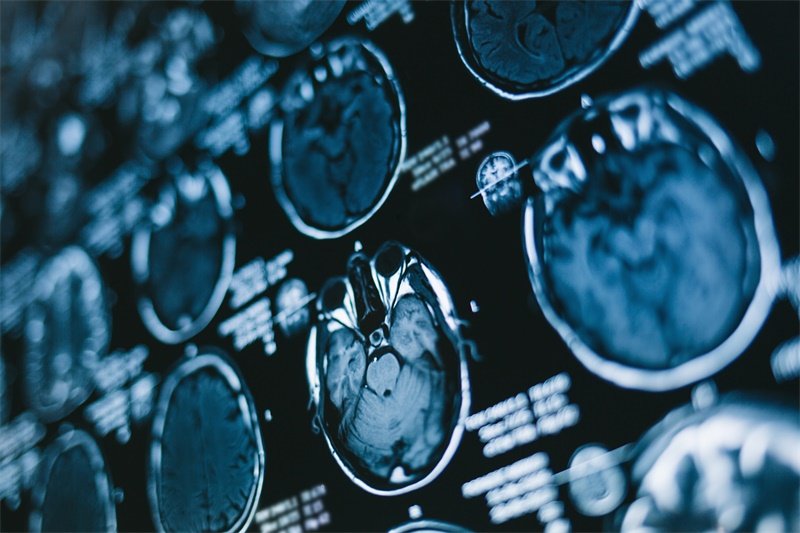

在对大脑镰右旁占位的诊断中,影像学检查是非常重要的手段。常用的检查方式包括磁共振成像(MRI)和计算机断层扫描(CT)。这些技术不仅可以帮助观察大脑结构的变化,还能够确定占位性病变的性质。

通过影像学检查,医生能够评估病变的大小、形状及与周围组织的关系。这些信息对后续的临床治疗方案制定及预后评估至关重要。